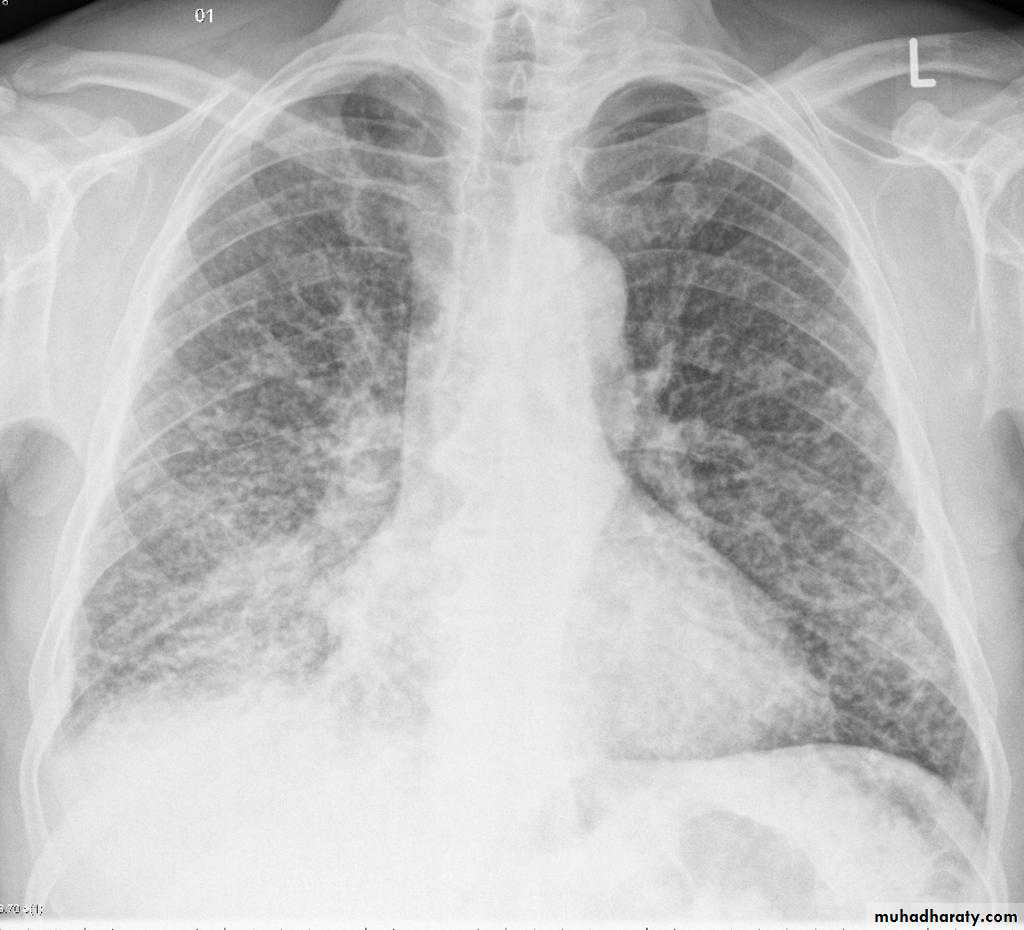

Miliary TB

65.Miliary TB

66. miliary TB